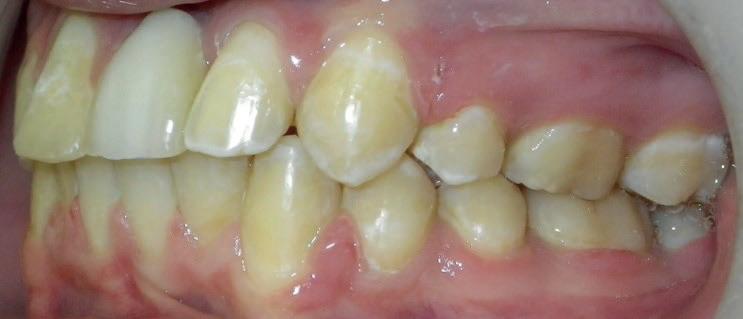

RECONFIGURAREA suportului osos implantar. În cazul prezentat, după ani de terapie ortodontică incorect executată, dezvoltarea dentară a pacientului a complicat obținerea unui zâmbet estetic. S-a reanalizat și s-a optat pentru abordare interdisciplinară care cuprinde chirurgia parodontală, un al doilea tratament

ortodontic și protetica pentru a oferi îngrijirea comprehensivă.